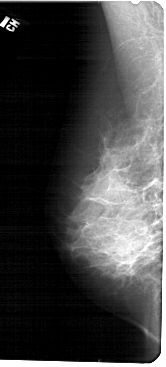

LEFT_MLO LINES 5491 PIXELS_PER_LINE 2476 BITS_PER_PIXEL 12 RESOLUTION 43.5 NON_OVERLAY